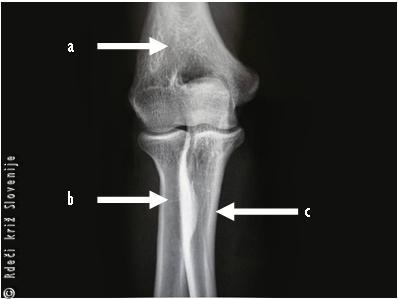

Slika 8

Rentgenska slika komolca

(a - nadlahtnica, b - koželjnica, c - podlahtnica).